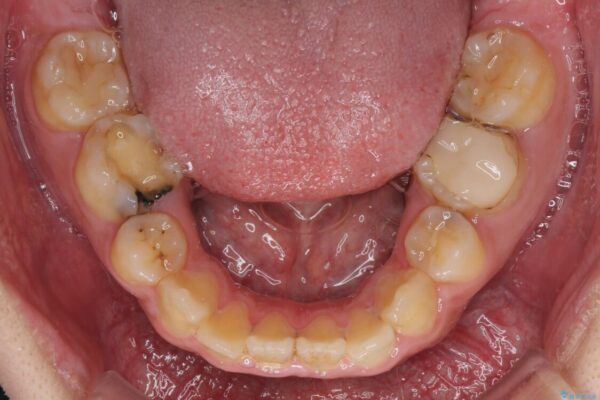

高校時代に行った抜歯矯正が後戻りをしたとのことで来院された患者様です。

治療前

• 後戻りでデコボコの前歯 インビザライン矯正治療 治療前画像